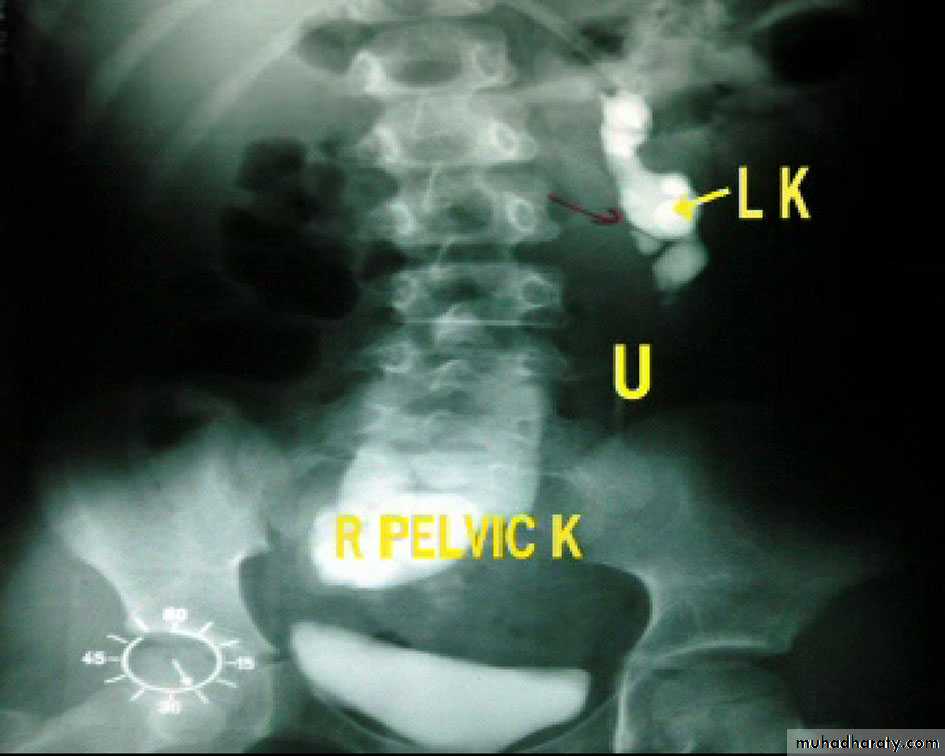

Ectopic kidney:

- Result from halted ascend of kidneys during fetal development

- Often are incidental findings during routine ultrasound, -usually located in the lower abdomen and rotated, -short ureter.

-Chronic pyelonephritis, calculi and hydronephrosis are more common .

Horse shoe kidney -Kidneys may fail to separate.

-Almost invariably the lower poles remain fused.

-The kidneys axes are more parallel to the spine and malrotated.